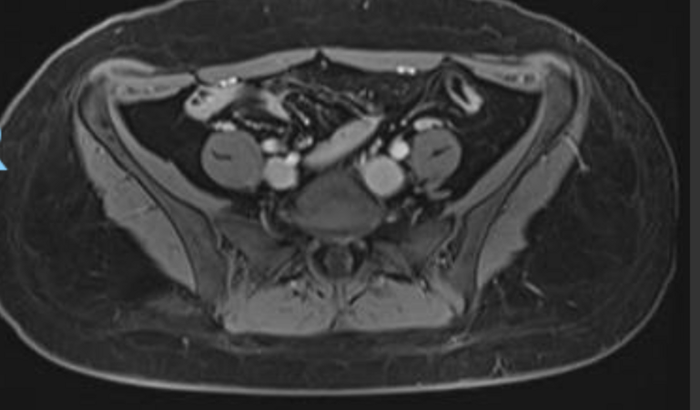

Eu sou Ana Beatriz, 32 anos, Carioca, mãe do Davi de 15 anos. A 1 mês descobri um tumor borderline, e desde então tenho tentado pelo sus a remoção deste tumor no ovário esquerdo, pois é indicado a cirurgia devido o crescimento rápido desse tumor e a preocupação dos órgão que ele está comprimindo. Devido a demora que será no SUS, não posso esperar segundo orientação médica, terei que fazer particular, e o total hoje é R$20.800,00, podendo ultrapassar caso na Biópsia na hora da cirurgia, seja constatado malignidade. Constatado benignidade, a cirurgia se encerra e somente o pós operatório fica. Saúde não se mede em real, mas foi uma surpresa assustadora, que chegou e não tenho opção de não fazer, ou ficar esperando. Deus abençoe sua vida, e sua contribuição.